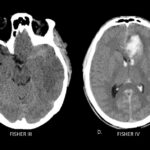

La escala de Fisher es un índice de riesgo de vasoespasmo basado en un patrón de hemorragia definido por tomografía sin contraste (TC) (ver Tabla 5), y la escala de Fisher modificada (también conocida como escala de Classen) es un índice similar de riesgo de isquemia cerebral tardía por vasoespasmo (ver Tabla 6).

| Tabla 6. Escala modificada de Fisher (Classen) en tomografía para la valoración de la HSA | |

| Grado | Patrón de HSA en TC de cerebro sin contraste |

| 0 | No HSA o hemorragia intraventricular (HIV) |

| 1 | Mínima HSA sin HIV |

| 2 | Mínima HSA con HIV bilateral |

| 3 | HSA gruesa (completo llenado de una o mas cisternas o cisuras) sin HIV bilateral |

| 4 | HSA gruesa (completo llenado de una o mas cisternas o cisuras) con HIV bilateral |

Claassen J, Bernardini GL, Kreiter K, et al. Effect of cisternal and ventricular blood on risk of delayed cerebral ischemia after subarachnoid hemorrhage: the Fisher scale revisited. Stroke 2001; 32:2012.

Fig. 1b. Escala de Fisher modificado en TC de cerebro sin contraste, cortes axiales. C. Fisher III y D. Fisher IV.